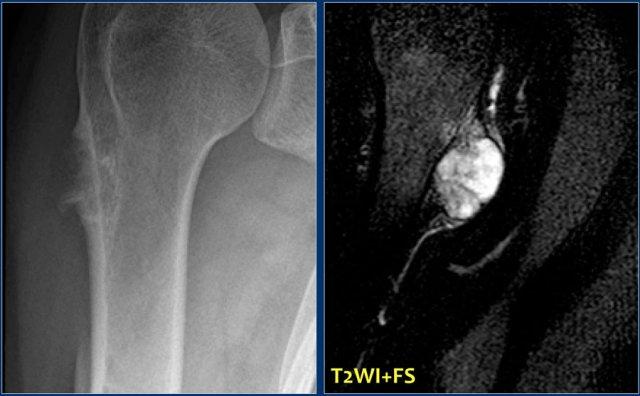

Phim X-quang cho thấy hình ảnh nhồi máu xương điển hình ở thân xương và hành xương của xương đùi và xương chày.

Trên hình ảnh MRI, nhồi máu xương được đặc trưng bởi các bờ không đều dạng rắn bò với tín hiệu thấp trên cả T1 và T2 WI, và tín hiệu mỡ từ trung bình đến cao ở phần trung tâm.

Tăng tín hiệu sau tiêm Gadolinium tĩnh mạch thường tối thiểu hoặc không có (xem hình bên phải).

Ở ngoại vi của ổ nhồi máu có thể thấy một vùng có cường độ tín hiệu tương đối cao trên T2WI.

Việc phân biệt nhồi máu xương với u sụn xương (enchondroma) hoặc u sụn xương ác tính độ thấp (low-grade chondrosarcoma) trên phim X-quang thường có thể rất khó khăn hoặc thậm chí không thể thực hiện được.

Các khối u sụn, đặc biệt là u sụn xương ác tính (chondrosarcoma), có thể biểu hiện hình ảnh xói mòn nội màng xương (endosteal scalloping), trong khi nhồi máu xương thì không có đặc điểm này.